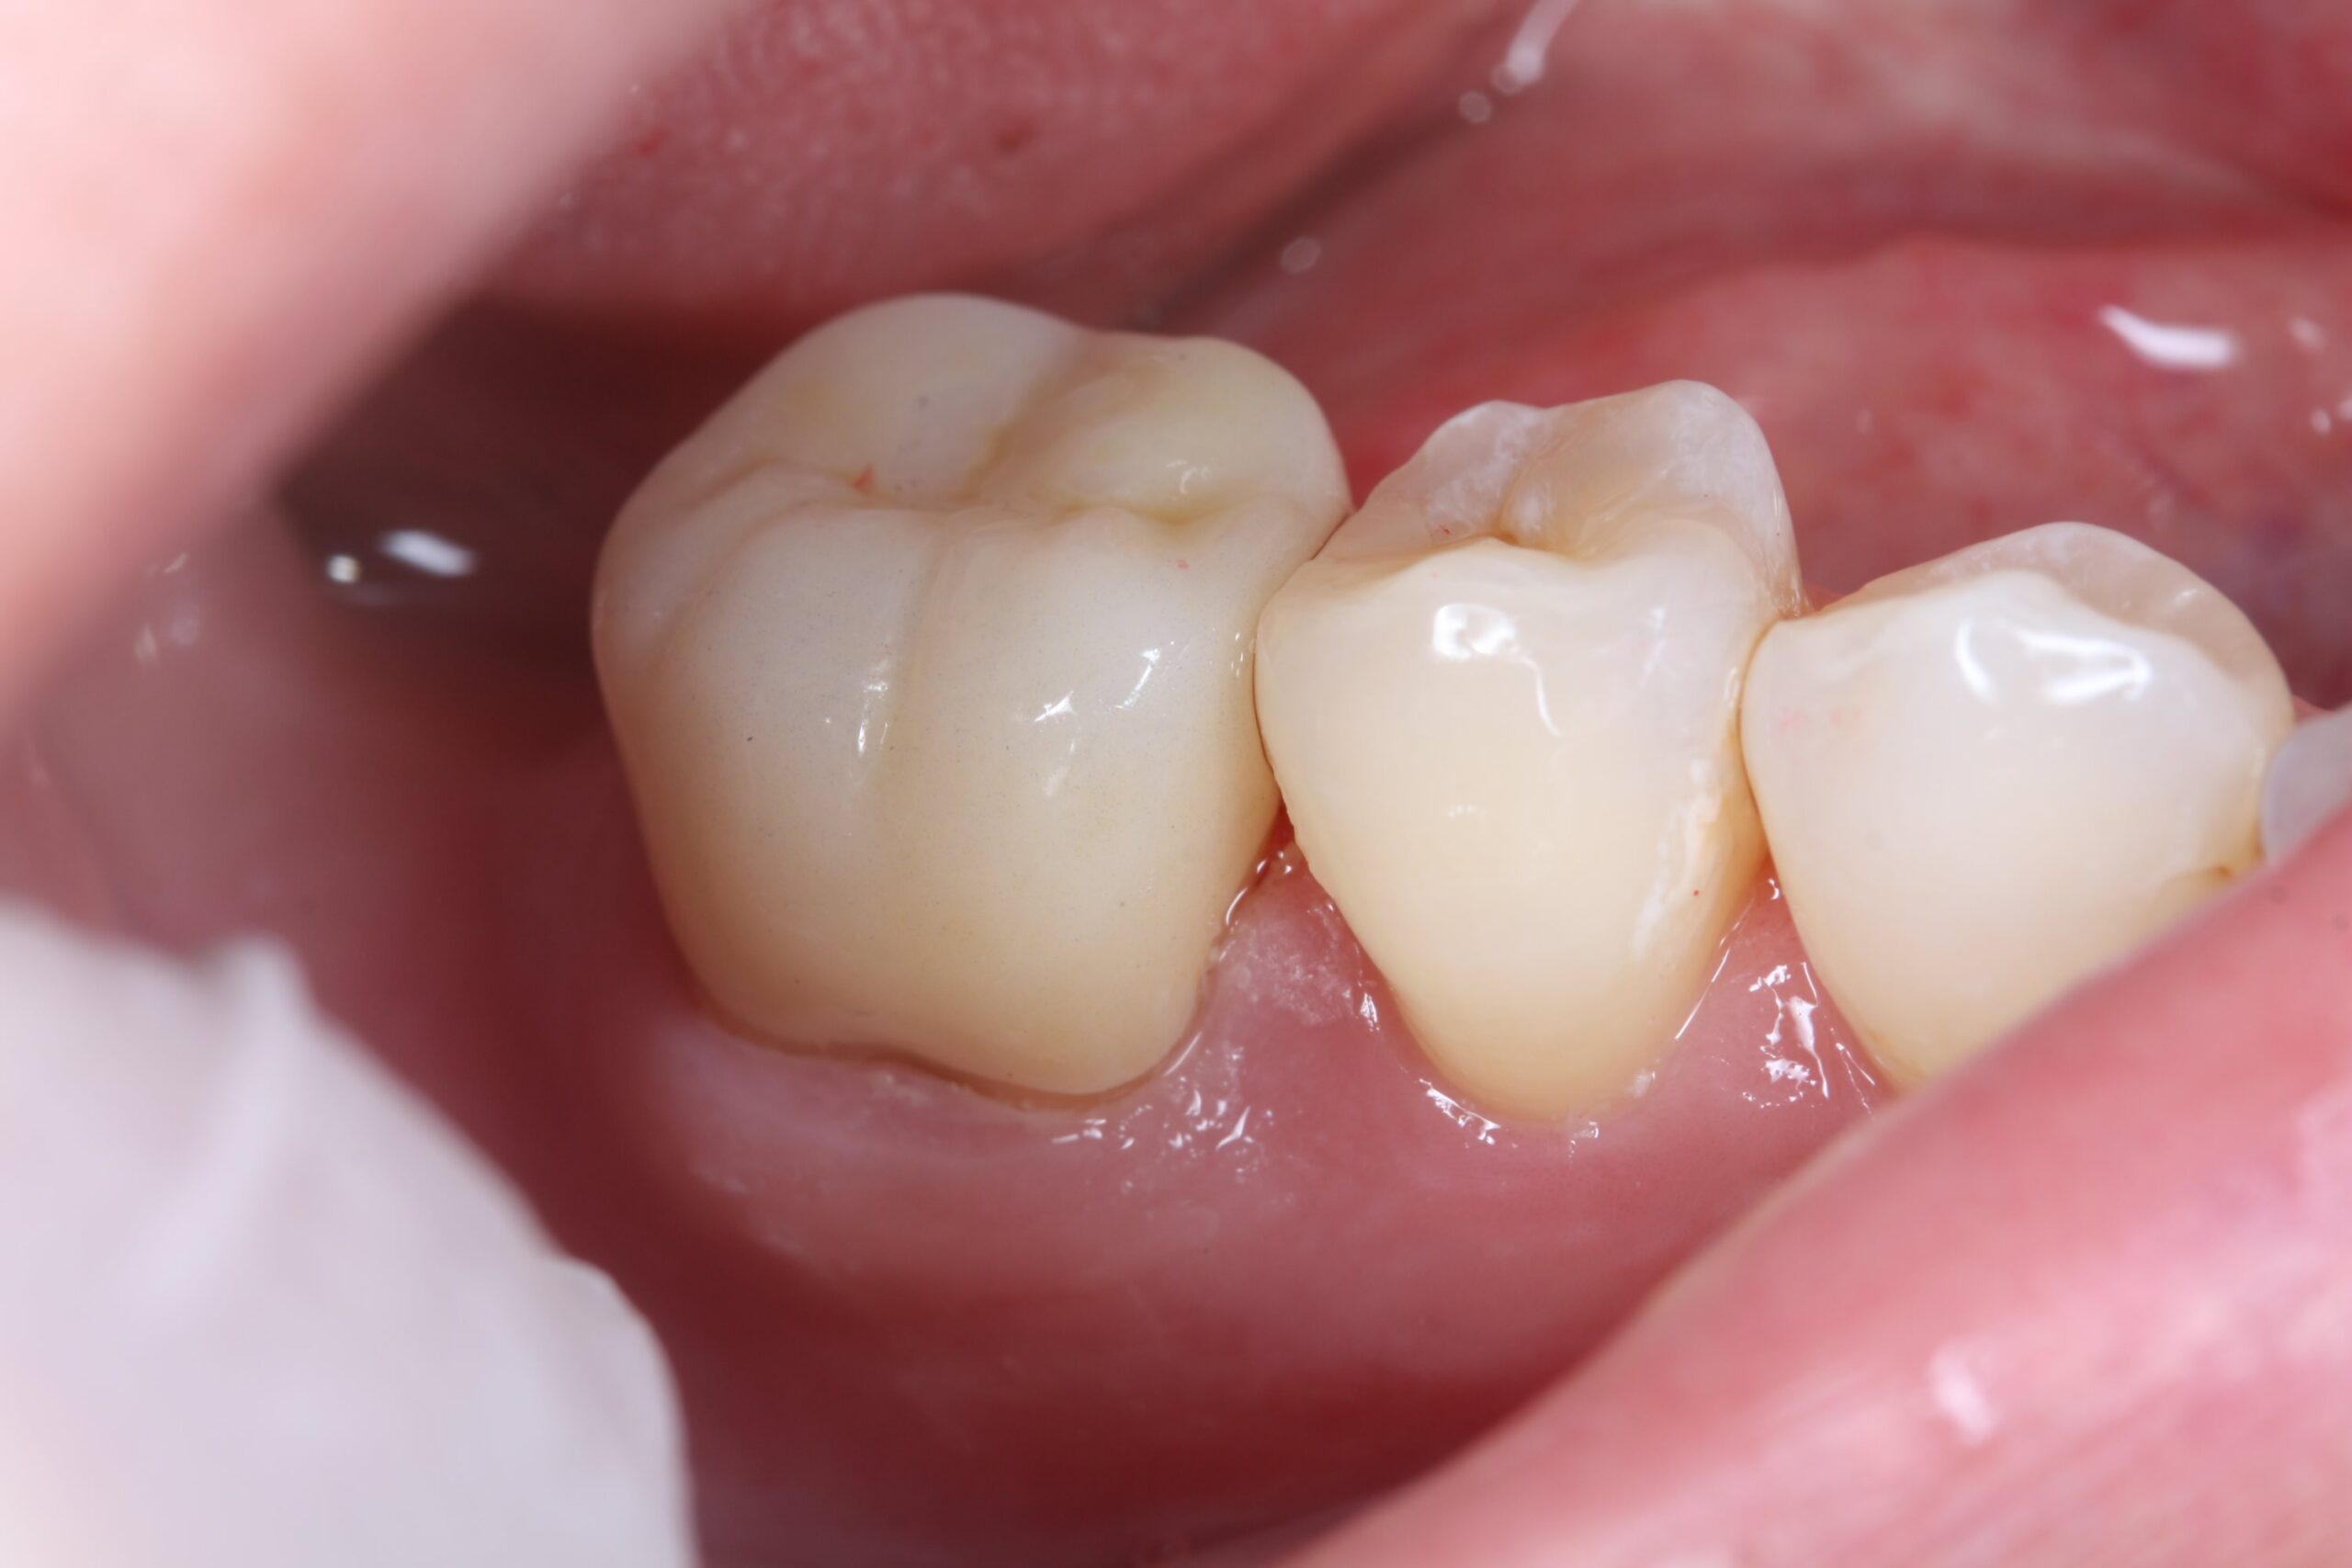

装着直後

色調や形態が周囲の歯と調和し、噛み合わせも確認したうえで装着しました。

本症例は、神経の治療を行なった後に、ジルコニアクランで噛み合わせを回復させました。

このように一番後ろの歯の治療の際には、噛む力に耐えられる材料を用いることが大切です。

患者様からは、「なるべく長く持つもの」「金属は避けたい」という要望がありましたので、ジルコニアクラウンを提案したところ、希望されました。

ジルコニアは通常のセラミックと比べると、透明感が若干劣りますが、強度があります。

患者様ご自身の歯も、比較的透明度が低いタイプでしたので、色調もマッチし、患者様もご満足されていました。奥歯は噛む力が強くかかる部位のため、神経の治療後には、歯を守るための被せ物選びが重要になります。